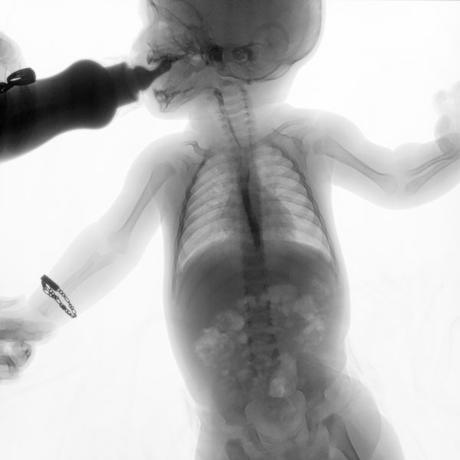

ESTUDIO SOLICITADO: SERIE ESOFAGOGASTRODUODENAL.

Se realiza Esofagograma con material de contraste baritado, por vía oral y por medio de control fluoroscópico se toman distintas proyecciones observando lo siguiente.

Se observa mecánica de la deglución con adecuado paso de medio de contraste de faringe a esófago sin presencia de defectos de llenado depósitos anómalos o fuga del mismo.

ESÓFAGO se observa de situación, calibre y trayecto normal. Contornos regulares y bien definidos. No se observan depósitos anómalos, defectos de llenado o fuga del medio de contraste.

UNION ESOFAGOGASTRICA se observa con calibre y situación normal. Sin observar reflujo a las maniobras de valsalva

ESTOMAGO se observa en su situación habitual, distendido, sin defectos de llenado.

- Actualmente no se demuestra Reflujo gastro-esofágico.

- Estudio de apariencia normal.